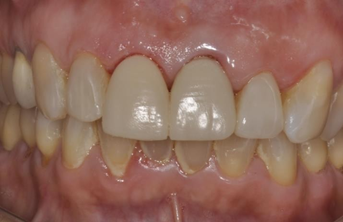

After complete polymerization of the cement, occlusion was checked with the aid of occlusal carbons and the cervical margins were cleaned with an exploratory probe. The cementation interface was finished and polished with abrasive rubbers of different granulations (Figure 12, 13 and 14).

Figure 12 Final aspect of the cemented restorations.

Figure 13 Final aspect of the cemented restorations.

Figure 14 Final aspect of the cemented restorations.